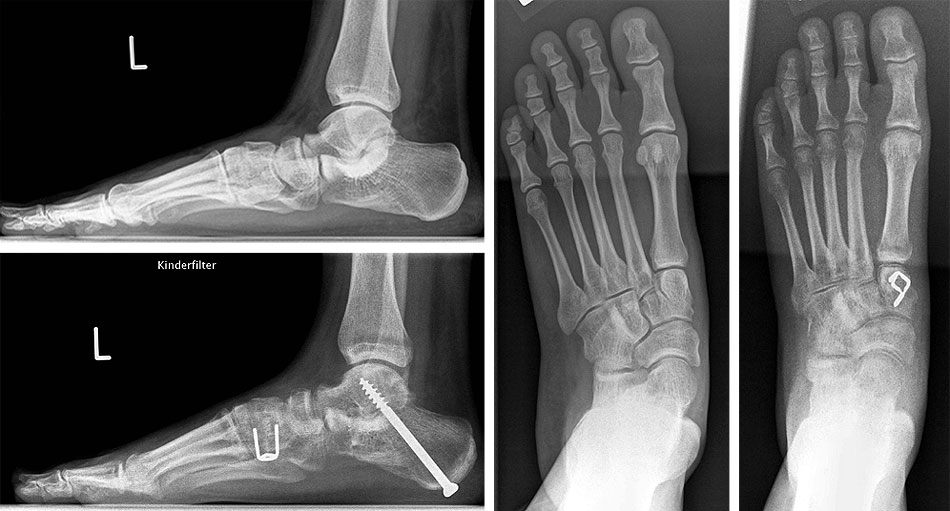

Zum Operationszeitpunkt 11-jähriger Junge mit großer Coalitio talocalcanearis (Längsausdehnung 25 mm, Querausdehnung 15 mm) und ausgeprägter kontrakter Planovalgus-Deformität (a und b). 4 Jahre nach Coalitio-Resektion, Fett-Interposition,

Abbildung 4

Nicht selten ist bei der Coalitio talocalcanealis zusätzlich eine Planovalgusdeformität zu beobachten. Die umfangreiche Literatur der vergangenen Jahrzehnte zur Coalitio beschrieb diese Kombination als prognostisch ungünstig für ein resezierendes Vorgehen, ließ bis vor wenigen Jahren die Frage des Vorgehens in diesen Fällen aber weitgehend offen. Luhmann und Schoenecker 8 berichteten von einem Fall sekundärer Calcaneus-Verlängerungsosteotomie, Hamel beschrieb 2009 die simultane Coalitio-Resektion und Calcaneus-Osteotomie an 9 Patienten im Kindes- und Jugendlichenalter 6 und berichtete später (2012)(Hamel 2012) über mittelfristige Ergebnisse mit Beschwerdefreiheit in 5 von 8 Fällen (Abb. 4); zwei Fälle hatten noch Beschwerden bei intensiver Belastung und in einem Fall mußte eine in-situ-Arthrodese sekundär durchgeführt werden. Blitz (2010) 9 stellte vier Fälle und Mosca und Bevan (2012) 4 zwei Fälle von Coalitio-Resektion und simultaner Calcaneus-Verlängerung vor mit jeweils überwiegend guten Ergebnissen. Giannini et al 10 berichteten über gute Ergebnisse nach Resektion und Einbringung eines Sinus-tarsi-Spacers zur Stellungskorrektur.

Insbesondere Mosca und Bevan weisen 4 auf die Möglichkeit hin, daß geklagte Beschwerden in diesen Fällen nicht immer durch die Coalitio selber, sondern z.T. mehr durch die Deformität ausgelöst sein können; sie beschreiben neun Fälle kindlich-jugendlicher Patienten, in denen sie mit einer Calcaneus-Verlängerung ohne Coalitio-Resektion überwiegend gute Ergebnisse im mittelfristigen Verlauf erzielen konnte.

Bei kombinierter Planovalgus-Deformität und Coalitio talocalcanealis sollte über eine primäre 96 (Hamel 2012) oder sekundäre 58 Korrektur durch Osteotomien mit oder ohne Resektion der Coalitio nachgedacht werden. Wird die Fehlstellung bei Resektion der Coalitio belassen, kann dies zu einer Dekompensation und Persistenz der Beschwerden beitragen, da das Subtalargelenk durch die Resektion einer größeren Coalitio erheblich destabilisiert wird.

Die Deformitäten-Korrektur richtet sich nach der Ausprägung der drei Komponenten der Planovalgus-Deformität in den drei Ebenen des Raumes: Das Standard-Korrektur-Verfahren stellt die „tarsale Triple-Osteotomie“ dar, bei der die Mittel-Vorfuß-Abduktion durch eine (leichte) Calcaneusverlängerung (Evans-Prozedur (Evans 1975)), die dann verbleibende Rückfuß-Valgus-Komponente durch eine Verschiebung des Tuber calcanei und die danach meist demaskiert zu beobachtende Mittel-Vorfuß-Supination durch eine plantarisierende Cuneiforme-mediale Osteotomie adressiert wird. Im Einzelfall kann sich je nach Ausprägung der Deformität eine der Osteotomien erübrigen.

Operatives Vorgehen: Nach Resektion der Coalitio (s.o.) wird über eine schräge Hautinzision über der lateralen Fußwurzel unter Schonung der Suralis-Äste und der Peronealsehnen der vordere Calcaneusabschnitt subperiostal umfahren. Nach Anbringen eines Distraktors erfolgt eine Osteotomie etwa 8 mm distal der vorderen Begrenzung der Gelenkfläche der hinteren Kammer des Subtalargelenkes. Hier wird je nach Ausmaß der Deformität ein trikortikaler Keil von ca. bis zu 5 bis 8 mm Basisbreite aus dem vorderen Beckenkamm eingebracht. Eine Sicherung des Calcaneocuboidgelenkes wie früher bei wesentlich ausgedehnteren Verlängerungen empfohlen erscheint nicht erforderlich. Die Rückfußvalgus-Komponente wird über eine separate Inzision im Bereich des lateralen Tuber calcanei durch medialisierende Osteotomie korrigiert. Im Kindes- und Jugendlichenalter ist eine Osteosynthese mit zwei perkutan von der Ferse aus eingebrachten Kirschner-Drähten ausreichend, wobei beide Drähte beide Calcaneus-Osteotomien stabilisieren. In aller Regel wird dann ein zweiter trikorticaler Span (ca. 5 mm Basisbreite) über einen dorsalen Zugang im Bereich des Os cuneiforme mediale in open-wedge-Technik zur Plantarisierung des medialen Strahles eingebracht. Hier ist eine Osteosynthese oft nicht erforderlich.